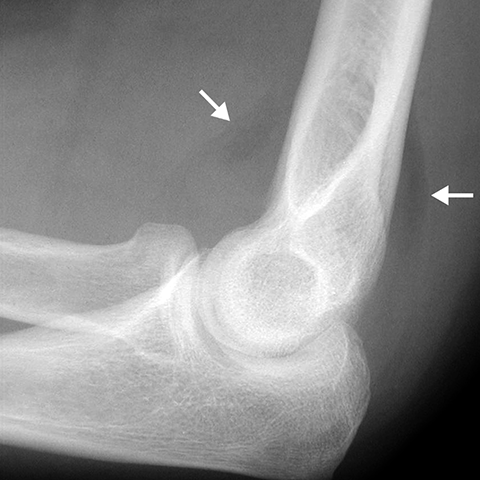

Radial Head fracture